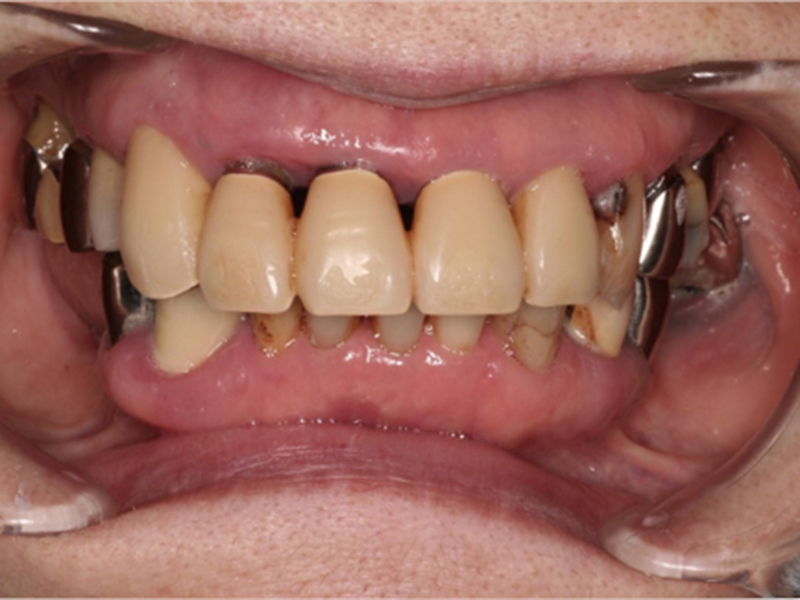

治療前の口腔内写真